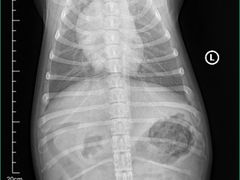

• 爱妮康宠物医院·干细胞免疫细胞·肿瘤·心脏(张江店)

• -爱妮康宠物医院·干细胞免疫细胞·肿瘤·心脏(张江店)